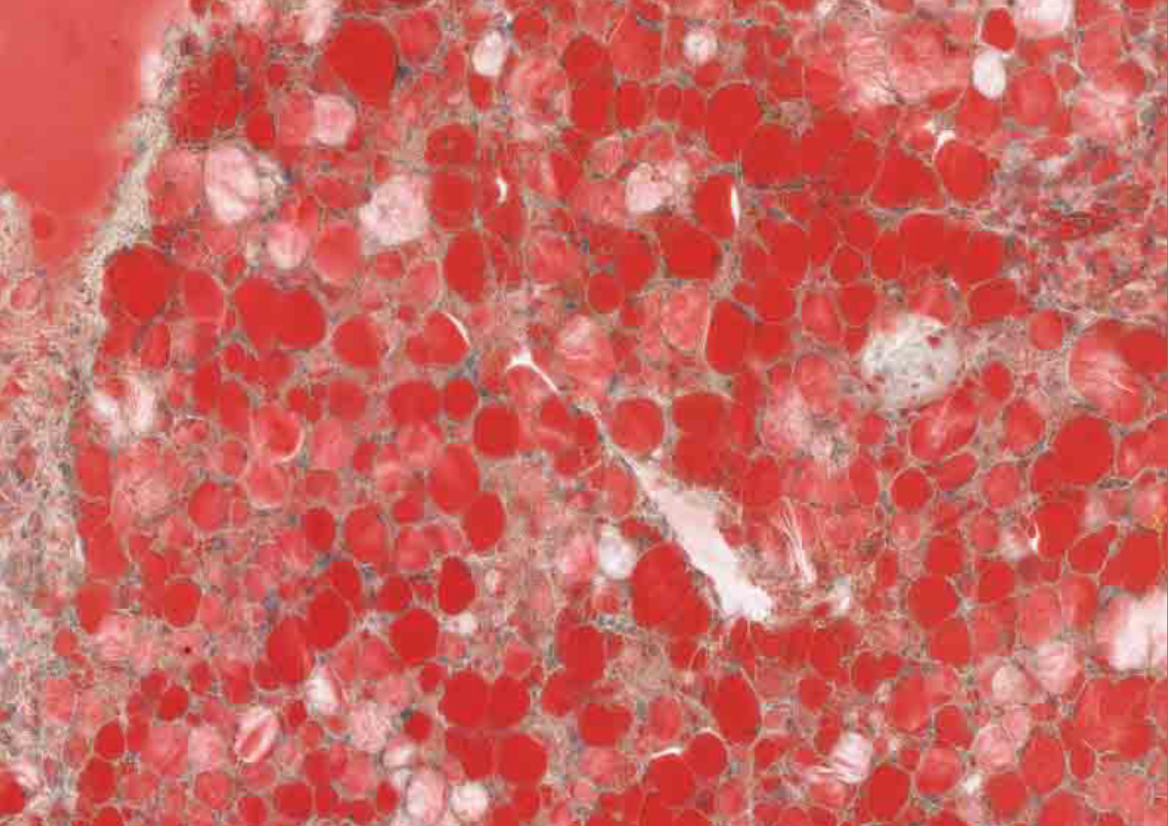

hémosidérose rénale